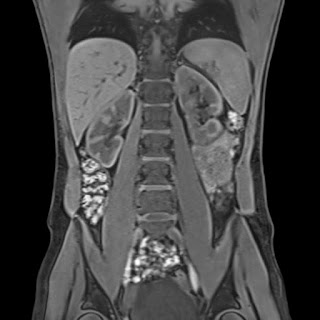

La tomografía computarizada es una prueba de diagnóstico por imágenes que utiliza una combinación de radiografías y tecnología computarizada para obtener imágenes de cortes transversales “rebanadas” del cuerpo, tanto horizontales como verticales. La TC muestra imágenes detalladas de los órganos internos, (huesos, tejidos blandos y vasos sanguíneos).

El uso de esta técnica de imagen presenta múltiples ventajas:

- Proporciona imágenes en tiempo real y se convierte en una herramienta útil para guiar procedimientos mínimamente invasivos.

- La exploración por TC ofrece información más detallada sobre lesiones, tumores y otras enfermedades que las radiografías convencionales.

- Permite identificar hemorragias internas, tumores, lesiones u otros daños.

Debido a las

facilidades en el diagnóstico de imágenes generalmente se realizan exámenes de: Cabeza, Cuello, Columna, Tórax, Pelvis, Abdomen, estructuras Oseas, miembros superiores e inferiores.

![]() |

| Tomografía de Cabeza - Corte Axial |

| Tomografía de Tórax - Corte Axial |